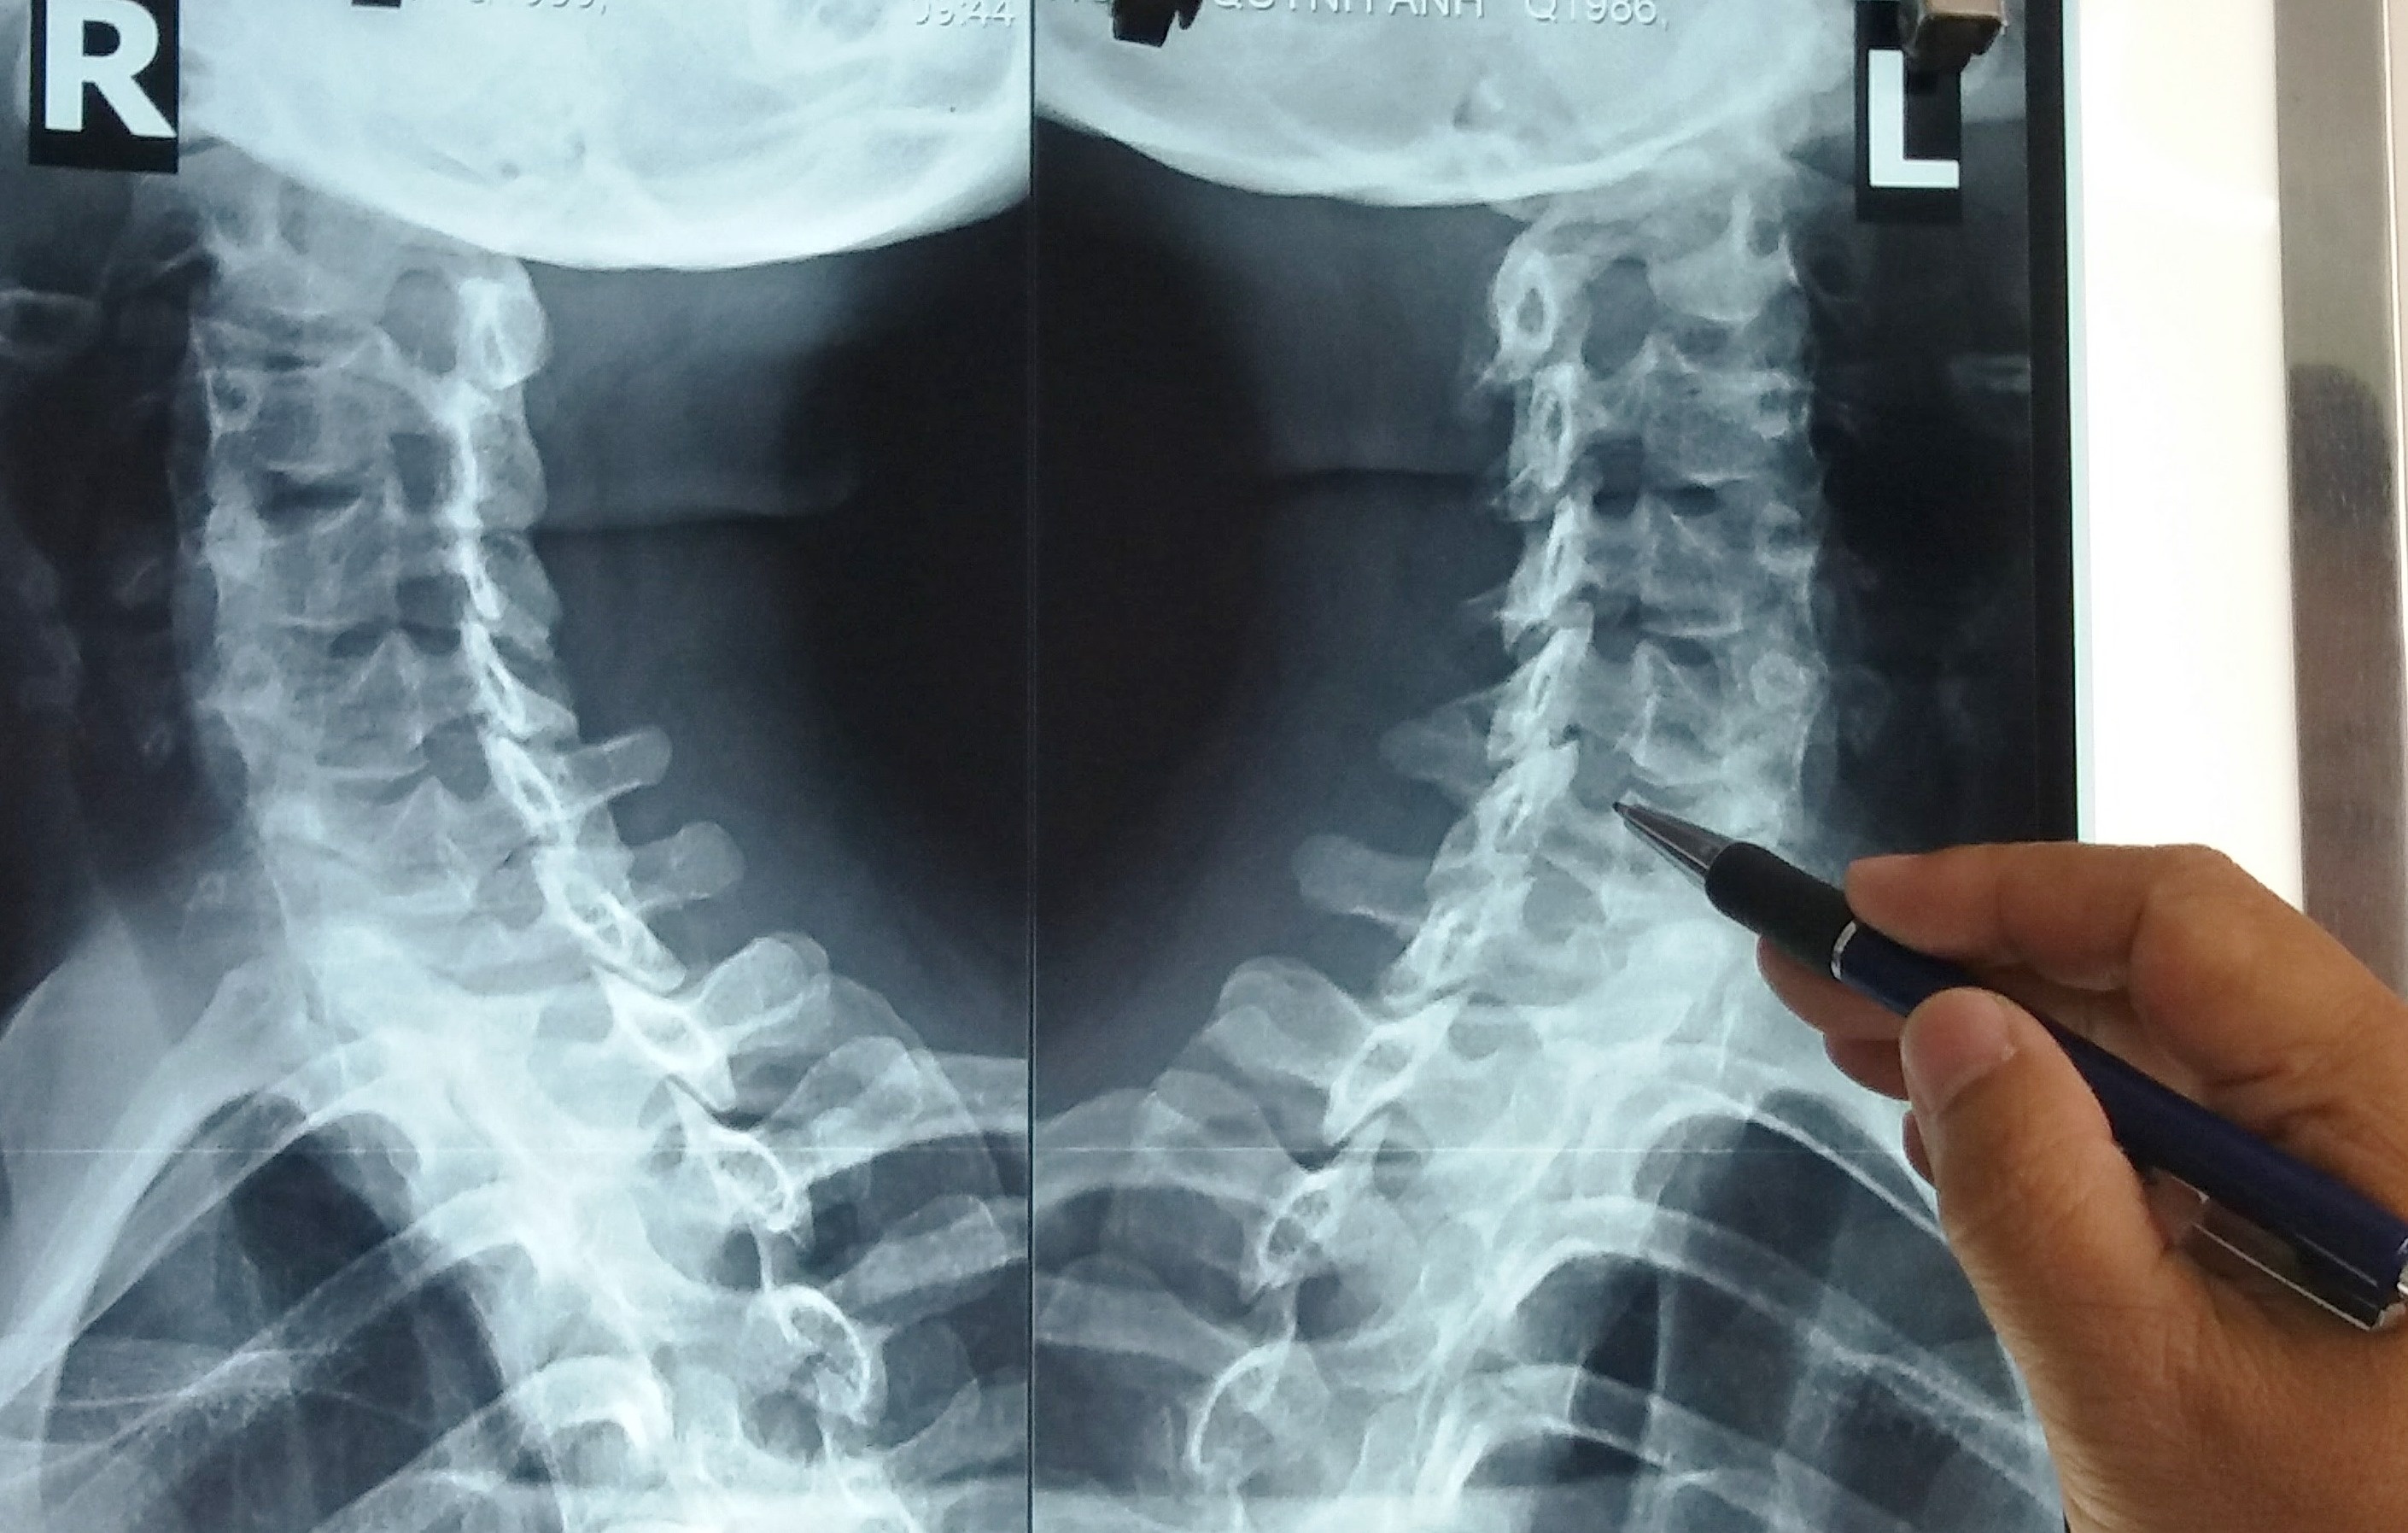

| Thường các bệnh lý thoái hóa đốt sống cổ ở người trẻ do những chèn ép tác động lên sụn khớp cổ vùng gáy. Ảnh: Bệnh viện cung cấp |